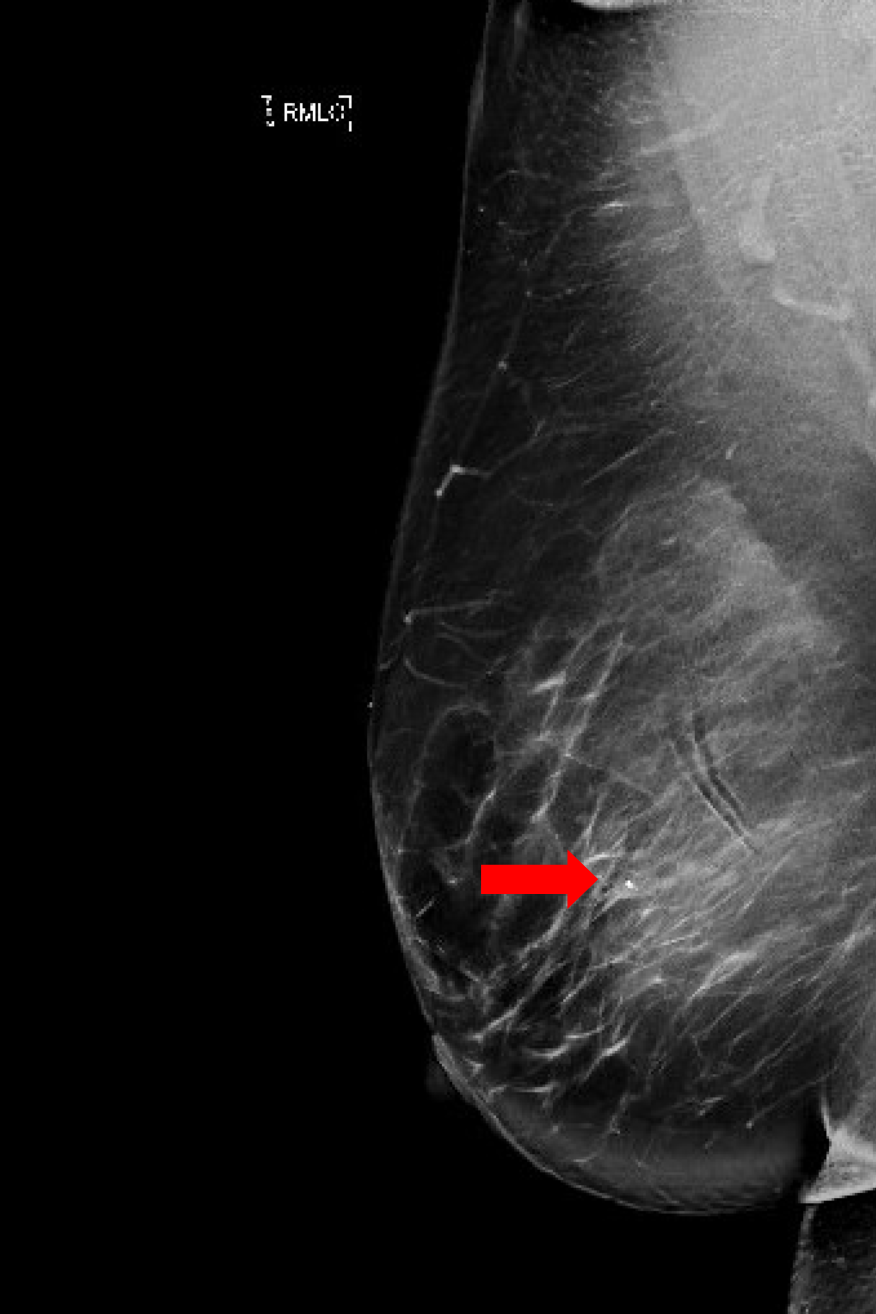

Este caso demuestra el procedimiento típico y los pasos clave para completar una mastectomía parcial (lumpectomía) con localización de Savi Scout. A través de una pequeña incisión, se extrajo todo el tejido necesario sin complicaciones. Las imágenes posteriores a la biopsia y de colocación de Savi Scout se mostraron en todo el caso para ayudar a dirigir la trayectoria general de la escisión; sin embargo, el Savi Scout fue vital para garantizar que solo elimináramos el área de interés. El área de preocupación se localizó con éxito en un área con la respuesta de radar más fuerte, y la disección hacia esta región comenzó a través de la pequeña incisión en la piel. Una vez que la sonda midió la distancia necesaria desde el marcador Savi para indicar que el área de la biopsia estaba correctamente localizada, la región se diseccionó meticulosamente del tejido mamario restante como un pequeño "cubo". Durante la disección de cada lado, el Savi Scout se identificó repetidamente en el tejido mamario aislado mediante el uso de la sonda. Se produjo una pérdida mínima de sangre y se requirió muy poca hemostasia al finalizar la operación. En total, el paciente tuvo un tiempo operatorio total de aproximadamente 1 hora. La orientación se mantuvo durante toda la tumorectomía y cada lado del "cubo" se marcó con los colores de tinta estandarizados para la patología. El espécimen se radiografió intraoperatoriamente dentro de un gabinete de rayos X portátil, donde se obtuvieron imágenes tanto del clip de biopsia como del marcador Savi Scout (Figura 4). El tejido extirpado se envió a anatomía patológica, para que se confirmara el diagnóstico final de papiloma intraductal sin atipia.

Figura 4. Radiografía intraoperatoria de la masa extirpada. Se utiliza para confirmar el área de la biopsia con el clip enrollado (flecha), y se retira el Savi Scout previamente colocado, en forma de barra (estrella). Cuando sea necesario, las radiografías posteriores a la escisión también revelarán si queda algún resto de tejido preocupante presente en los márgenes de la masa extirpada.